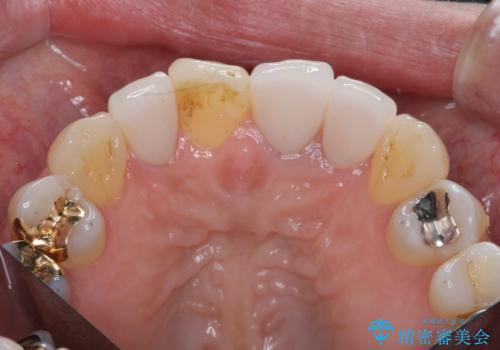

装着されているセラミッククラウンを除去したのち、現在の歯ぐきのラインにしっかりと合う精度の高いオールセラミッククラウンを作製していきます。

周囲の歯に調和したセラミッククラウンを作製し、審美性を大幅に向上させることができました。